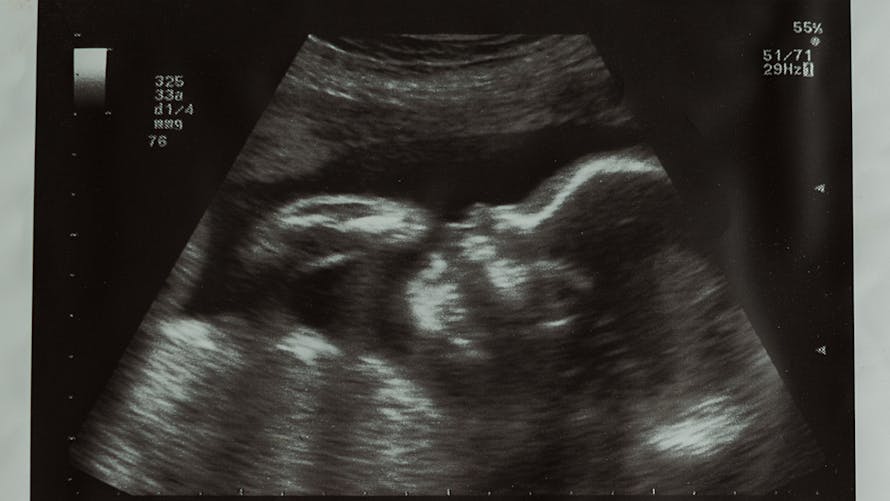

Développement du fœtus 12 semaines de grossesse Le visage de votre bébé ressemble de plus en plus à un visage humain Pourtant, il ne mesure encore que 5,5 centimètres de la tête au coccyx, et ne pèse même pas 14 grammes Les yeux, qui sont d'abord apparus sur les côtés de la tête, se sont rapprochés Les oreilles sont presqueVotre grossesse est encore récente, et pourtant, les premiers signes de dents apparaissent sous la forme de petits bourgeons à l'intérieur des gencives de votre bébé Vous avez probablement pris entre 12 et 15 lb (5 et 7 kg) À partir de maintenant, vous allez prendre du poids plus régulièrement, environ 225 grammes par semaineDe la 28ème (30 SA) à la 29ème (31 SA) semaine de grossesse Votre futur bébé est de plus sensible aux sons et aux gestes, mais il est de plus en plus à l'étroit dans votre ventre !

12 semaines de grossesse À quoi s'attendre Votre bébé à 12 semaines de grossesse Jusqu'au bout des ongles ! Votre bébé pendant la semaine 12 Le fœtus mesure actuellement environ 5 cm de la tête au coccyx (longueur craniocaudale ou LCC, mesurée lors de l'échographie), et 7 à 8 cm de la tête aux talons Il pèse environ 15 grammes Au cours des trois dernières semaines, votre bébé a plus que doublé de tailleVotre bébé mesure entre 10 et 12 cm et pèse environ 50 grammes

Les reins commencent à produire de l'urine et à la rejeter dans le liquide amniotique et la rate produit des globules rouges, qui servent à transporter l'oxygène dans le corps12 semaines de grossesse Croissance et développement de bébé La semaine 12 marque la fin du premier trimestre Il mesure environ 8 centimètres et pèse autour de 18 grammes Le coeur de votre bébé bat très rapidement, environ 160 pulsations par minute ou deux fois plus vite que les battements de la maman